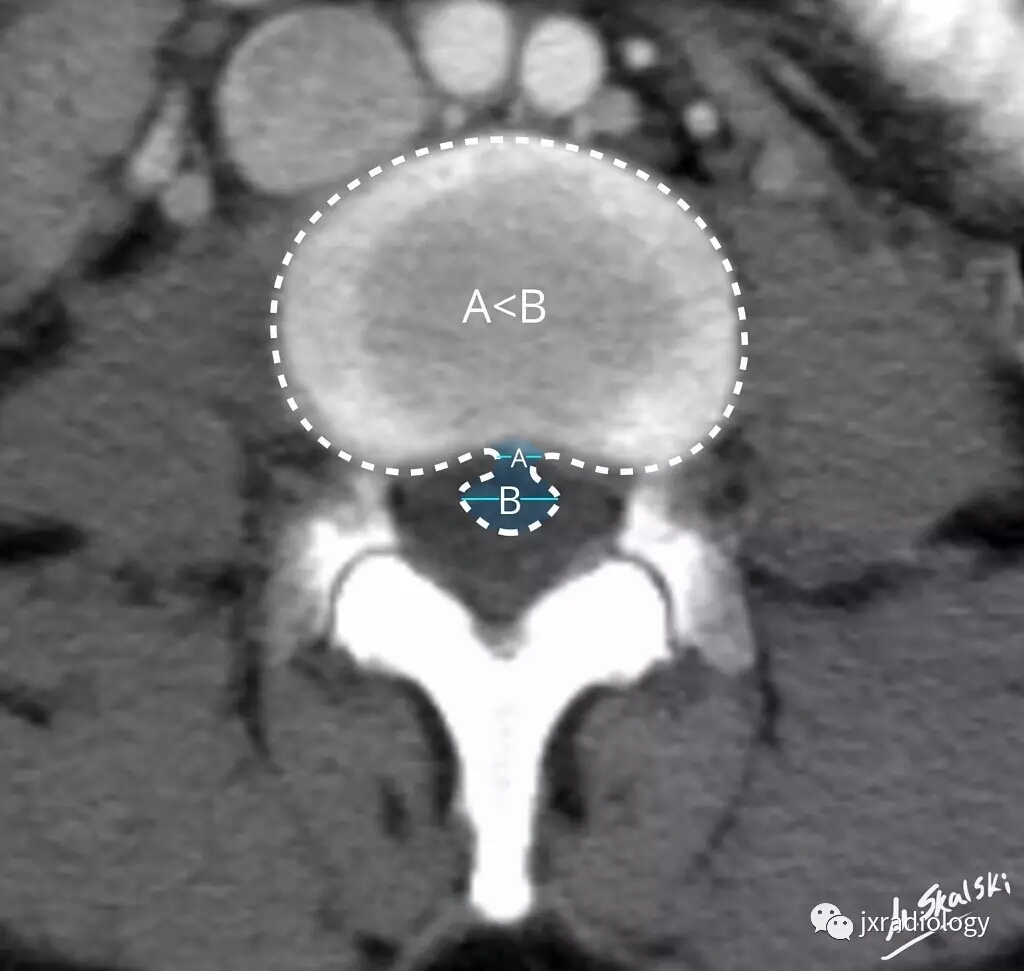

四、椎间盘突出亚型:椎间盘挤出(Disc extrusion)

移位椎间盘最大测量值大于其来源的基底部